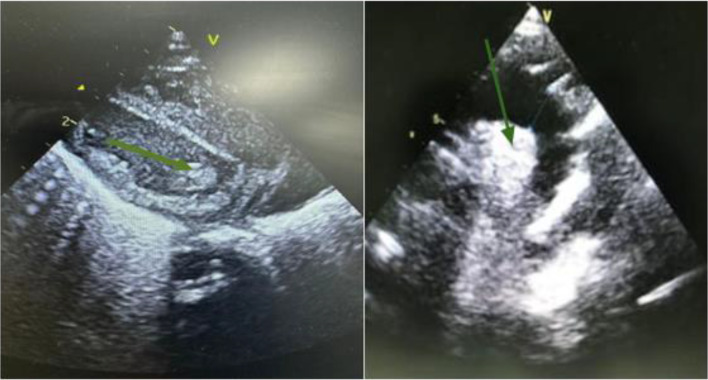

Serratia marcescens (S. marcescens) is a Gram-negative rod-shaped bacterium belonging to the Enterobacteriaceae family, commonly found in various environments. This opportunistic pathogen can cause urinary tract infections, respiratory infections and septicaemia, but endocarditis is particularly rare and concerning due to its rapid and devastating progression. We report the first documented case worldwide of infective endocarditis (IE) caused by S. marcescens producing NDM-type carbapenemase, and the second reported case of S. marcescens endocarditis in a preterm infant. The patient was a preterm male infant born at 34 weeks of gestation, from a triplet pregnancy, admitted to the neonatal intensive care unit on day 2 of life for respiratory distress. The mother, aged 39, had undiagnosed gestational diabetes. Premature rupture of membranes had occurred 10 days before delivery, necessitating prophylactic treatment with amoxicillin. On day 4 of life, the newborn developed a fever with elevated C-reactive protein (CRP) levels and leucocytosis, leading to antibiotic therapy with colistin, imipenem and amikacin. Blood cultures revealed the presence of carbapenemase-producing S. marcescens sensitive to fluoroquinolones. A cardiac ultrasound showed a vegetation on the mitral valve, confirming the diagnosis of IE. Despite intensive treatment, the newborn died on day 16 of life due to septic shock. This rare case of endocarditis caused by S. marcescens highlights the severity of this infection in preterm infants. Treatment relies on appropriate antibiotic therapy. Prevention requires strict hygiene measures. Further research is needed to establish optimal therapeutic recommendations.